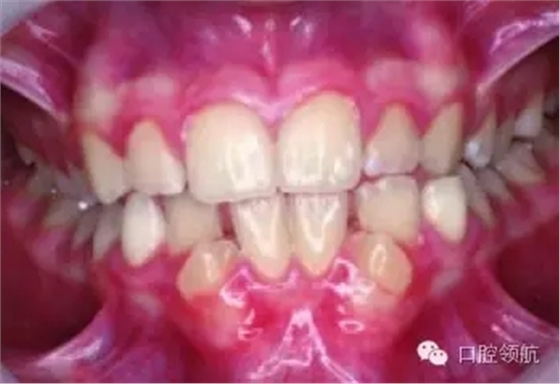

圖2.9中明顯的牙列異常有哪些?

雙側(cè)下頜側(cè)切牙和尖牙移位。

圖2.9